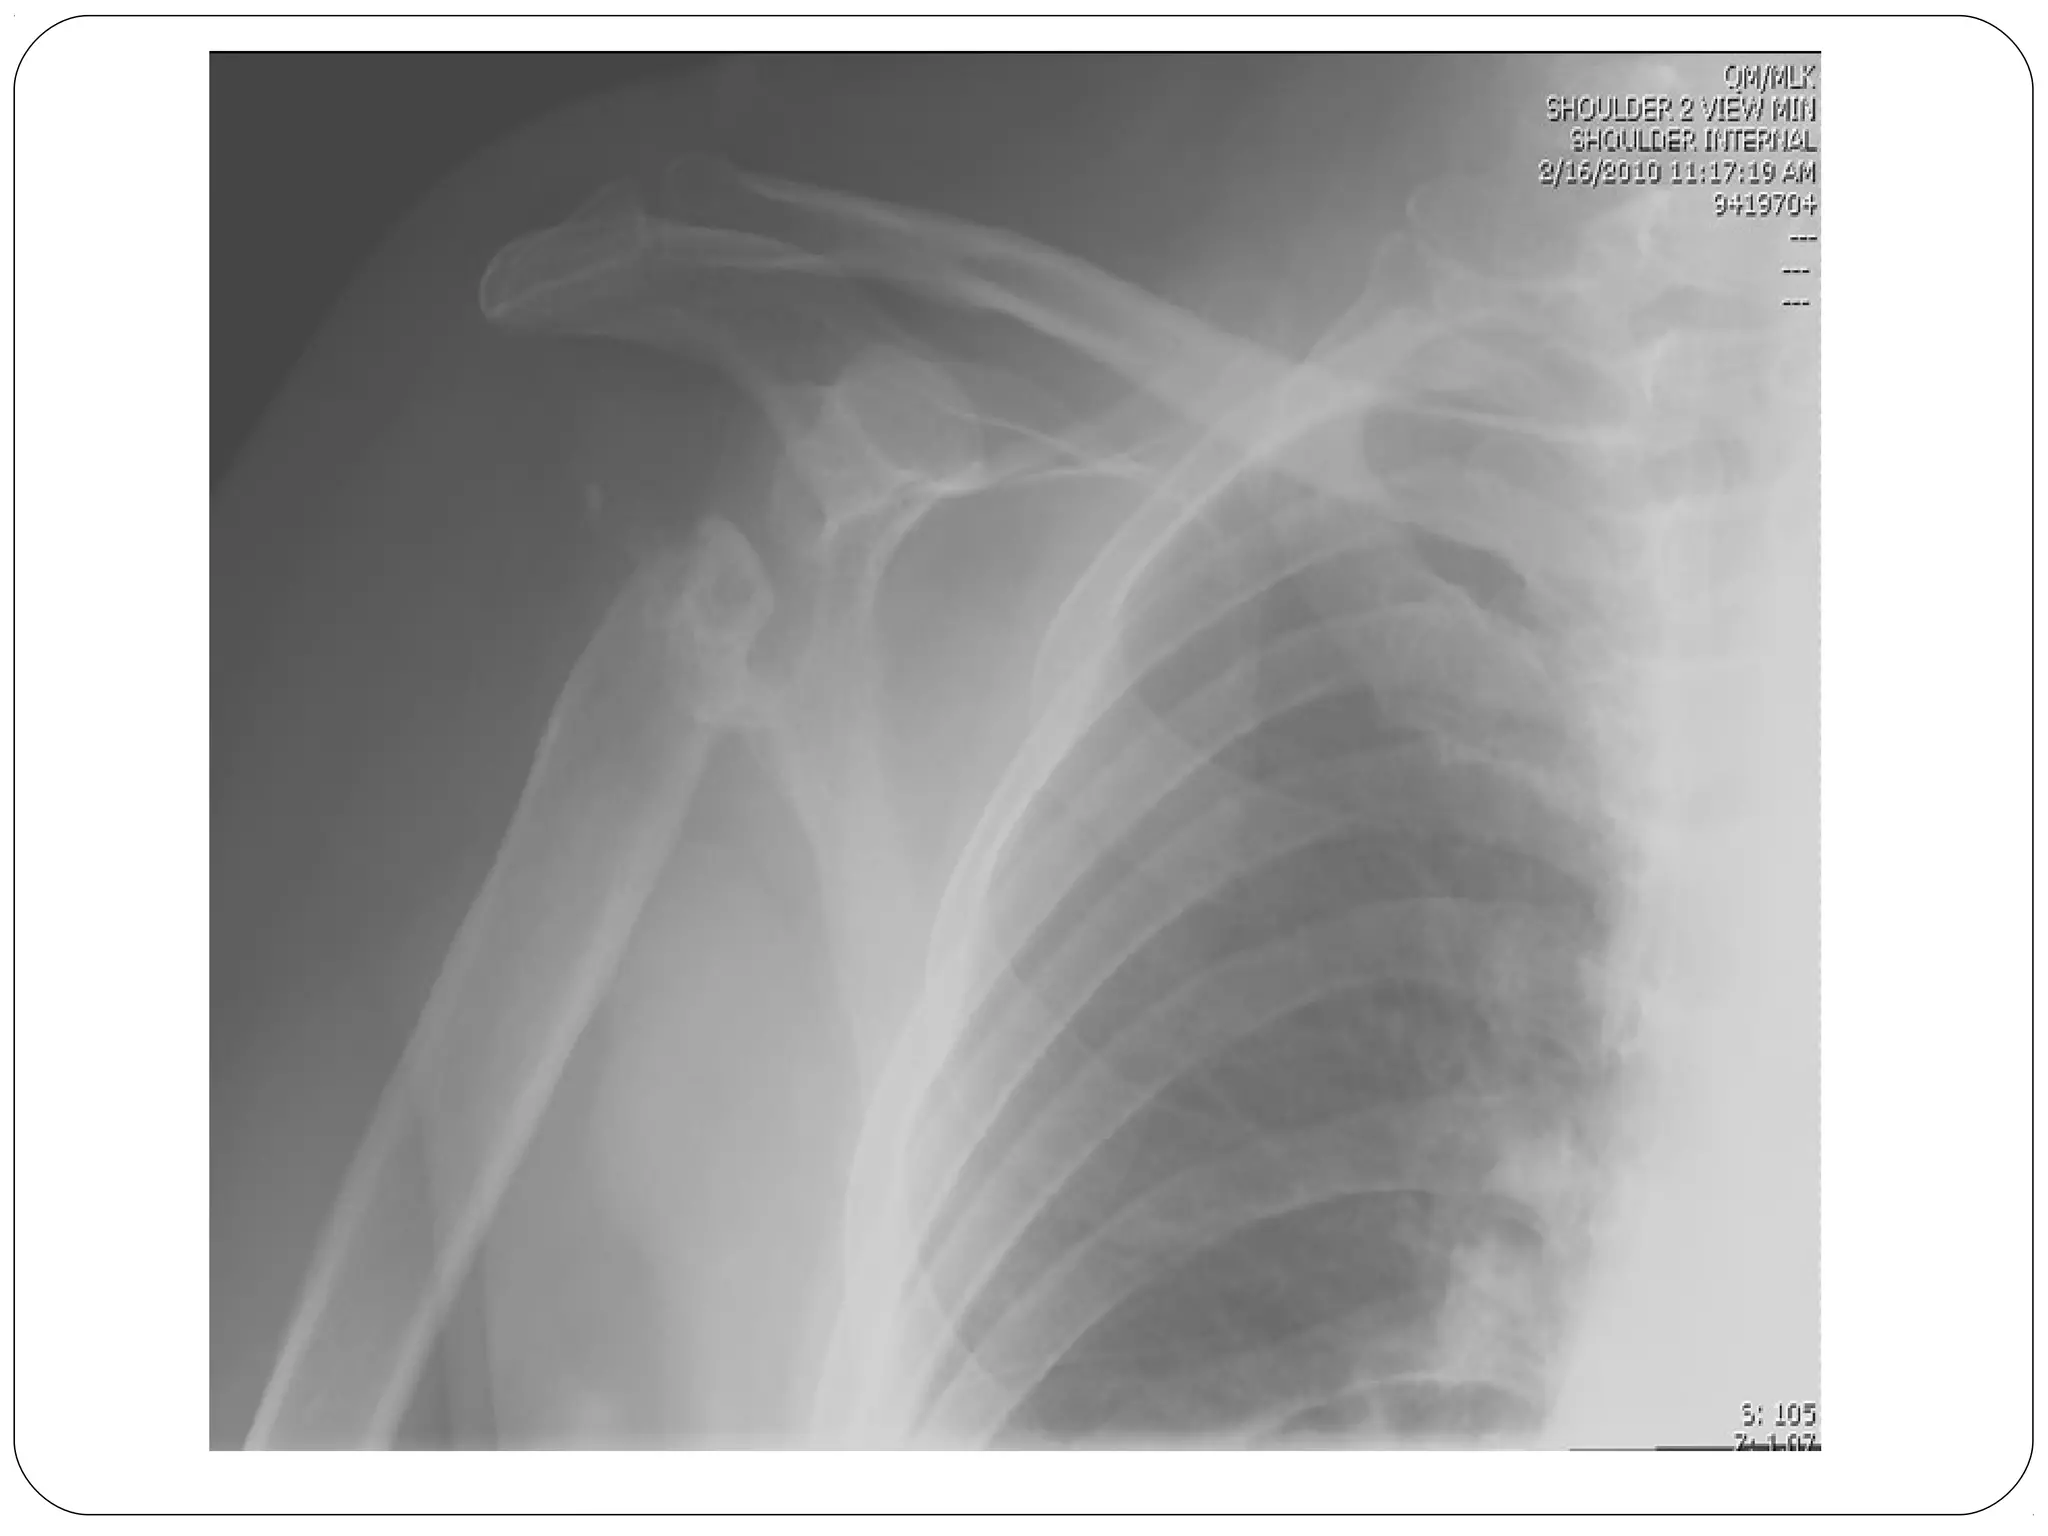

Viewing Images

Therefore, “One View is No View”

Two views are needed, ideally at 90

degress to one another for proper 3-D

like interpretation